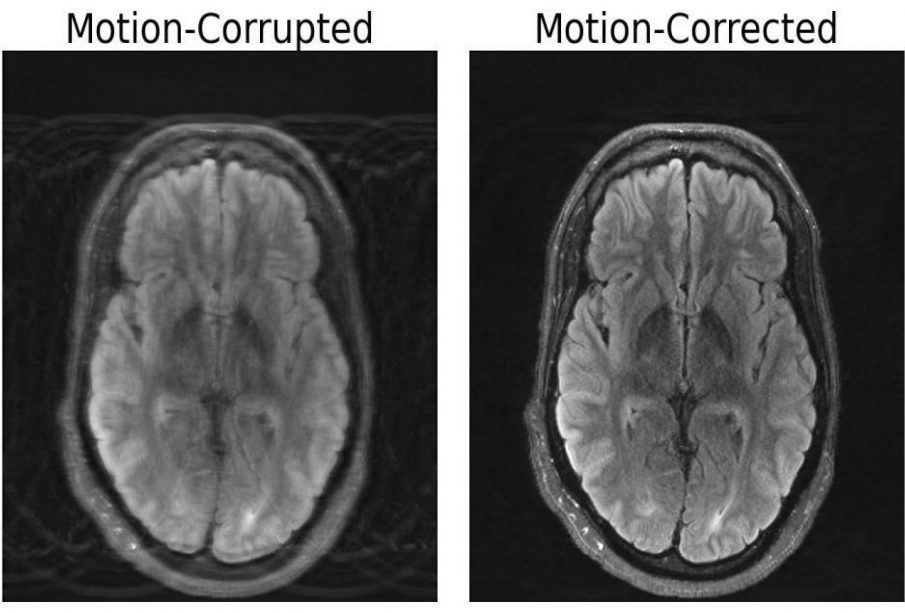

Compared to other imaging modalities like X-rays or CT scans, MRI scans provide high-quality soft tissue contrast. Unfortunately, MRI is highly sensitive to motion, with even the smallest of movements resulting in image artifacts. These artifacts put patients at risk of misdiagnoses or inappropriate treatment when critical details are obscured from the physician. But researchers at MIT may have developed a deep learning model capable of motion correction in brain MRI.

The paper, titled “Data Consistent Deep Rigid MRI Motion Correction,” was recently awarded best oral presentation at the Medical Imaging with Deep Learning conference (MIDL) in Nashville, Tennessee. The method computationally constructs a motion-free image from motion-corrupted data without changing anything about the scanning procedure. “Our aim was to combine physics-based modeling and deep learning to get the best of both worlds,” Singh says.

The importance of this combined approach lies within ensuring consistency between the image output and the actual measurements of what is being depicted, otherwise the model creates “hallucinations” — images that appear realistic, but are physically and spatially inaccurate, potentially worsening outcomes when it comes to diagnoses.